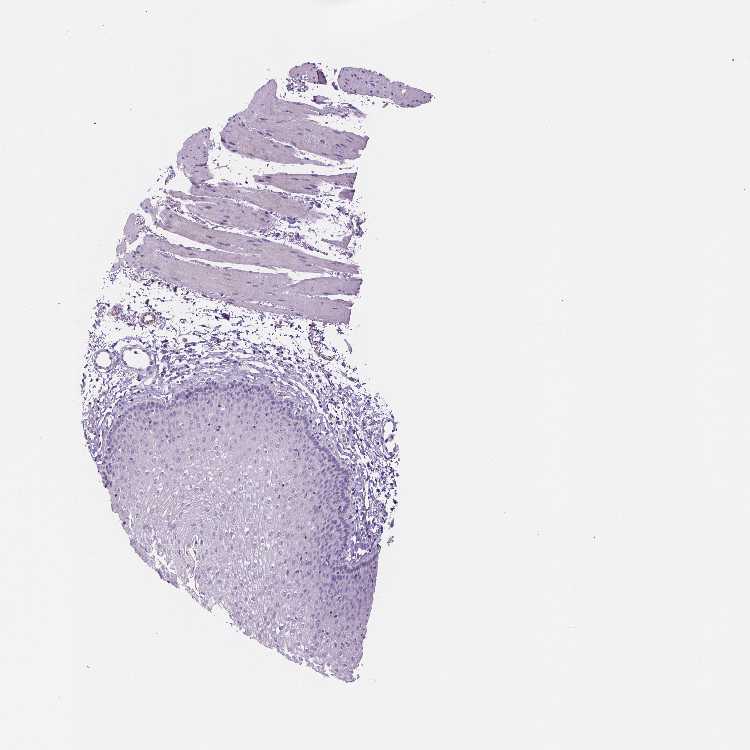

ESOPHAGUS - Antibody stainingi

Antibody staining in the annotated cell types in the current human tissue is reported as not detected, low, medium, or high, based on conventional immunohistochemistry profiling in selected tissues. This score is based on the combination of the staining intensity and fraction of stained cells.

Each image is clickable and will lead to virtual microscopy that enables deeper exploration of all samples and also displays staining intensity scores, fraction scores and subcellular localization as well as patient and tissue information for each sample.

Antibody HPA038171Antibody CAB006908

Squamous epithelial cells Not detectedNot detected